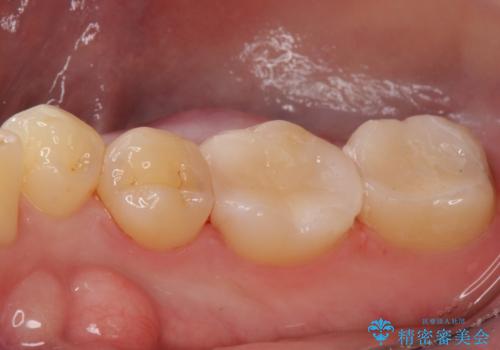

セラミックインレー。

- セラミック治療希望の患者様です。

古い樹脂の材料をとりe-maxの詰め物で治療を行いました。

適合の良い詰め物が入りました。